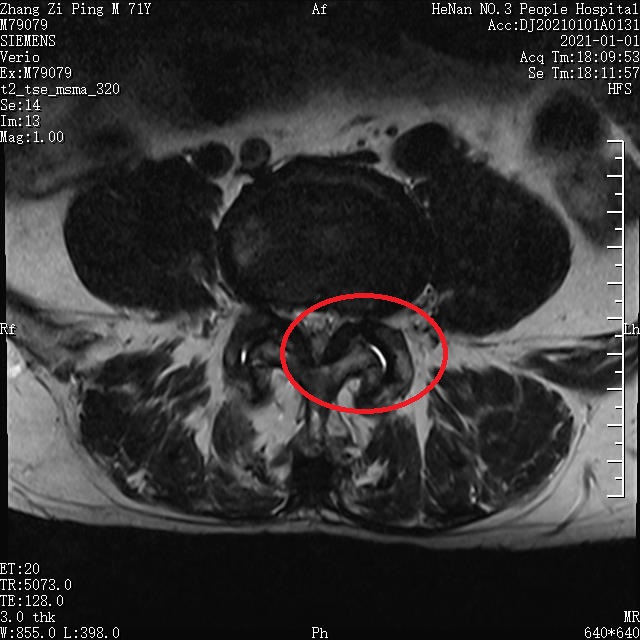

术前 CT

1623149390988114.jpg